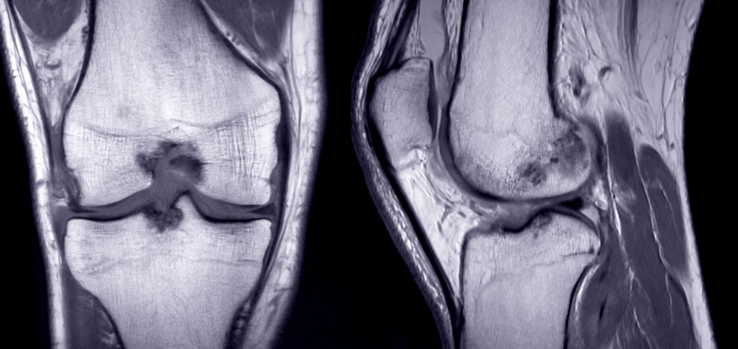

Diagnostika poškodb: kdaj je čas za MR kolena?

Ko bolečina vztraja, je priporočljivo opraviti natančnejšo diagnostiko, na primer z magnetno resonanco (MR) kolenskega sklepa. MR omogoča dobro sliko mehkih tkiv (hrustanec, vezi, kite) in je korak naprej pri razumevanju vzroka.

Magnetna resonanca (MR) je zlati standard, ko želimo videti:

- hrustanec,

- vezi,

- meniskus,

- kite in mehka tkiva.

Kdaj je MR smiselna?

- bolečina vztraja kljub počitku,

- koleno oteka,

- koleno “pobegne”,

- sum na meniskus ali vezi.